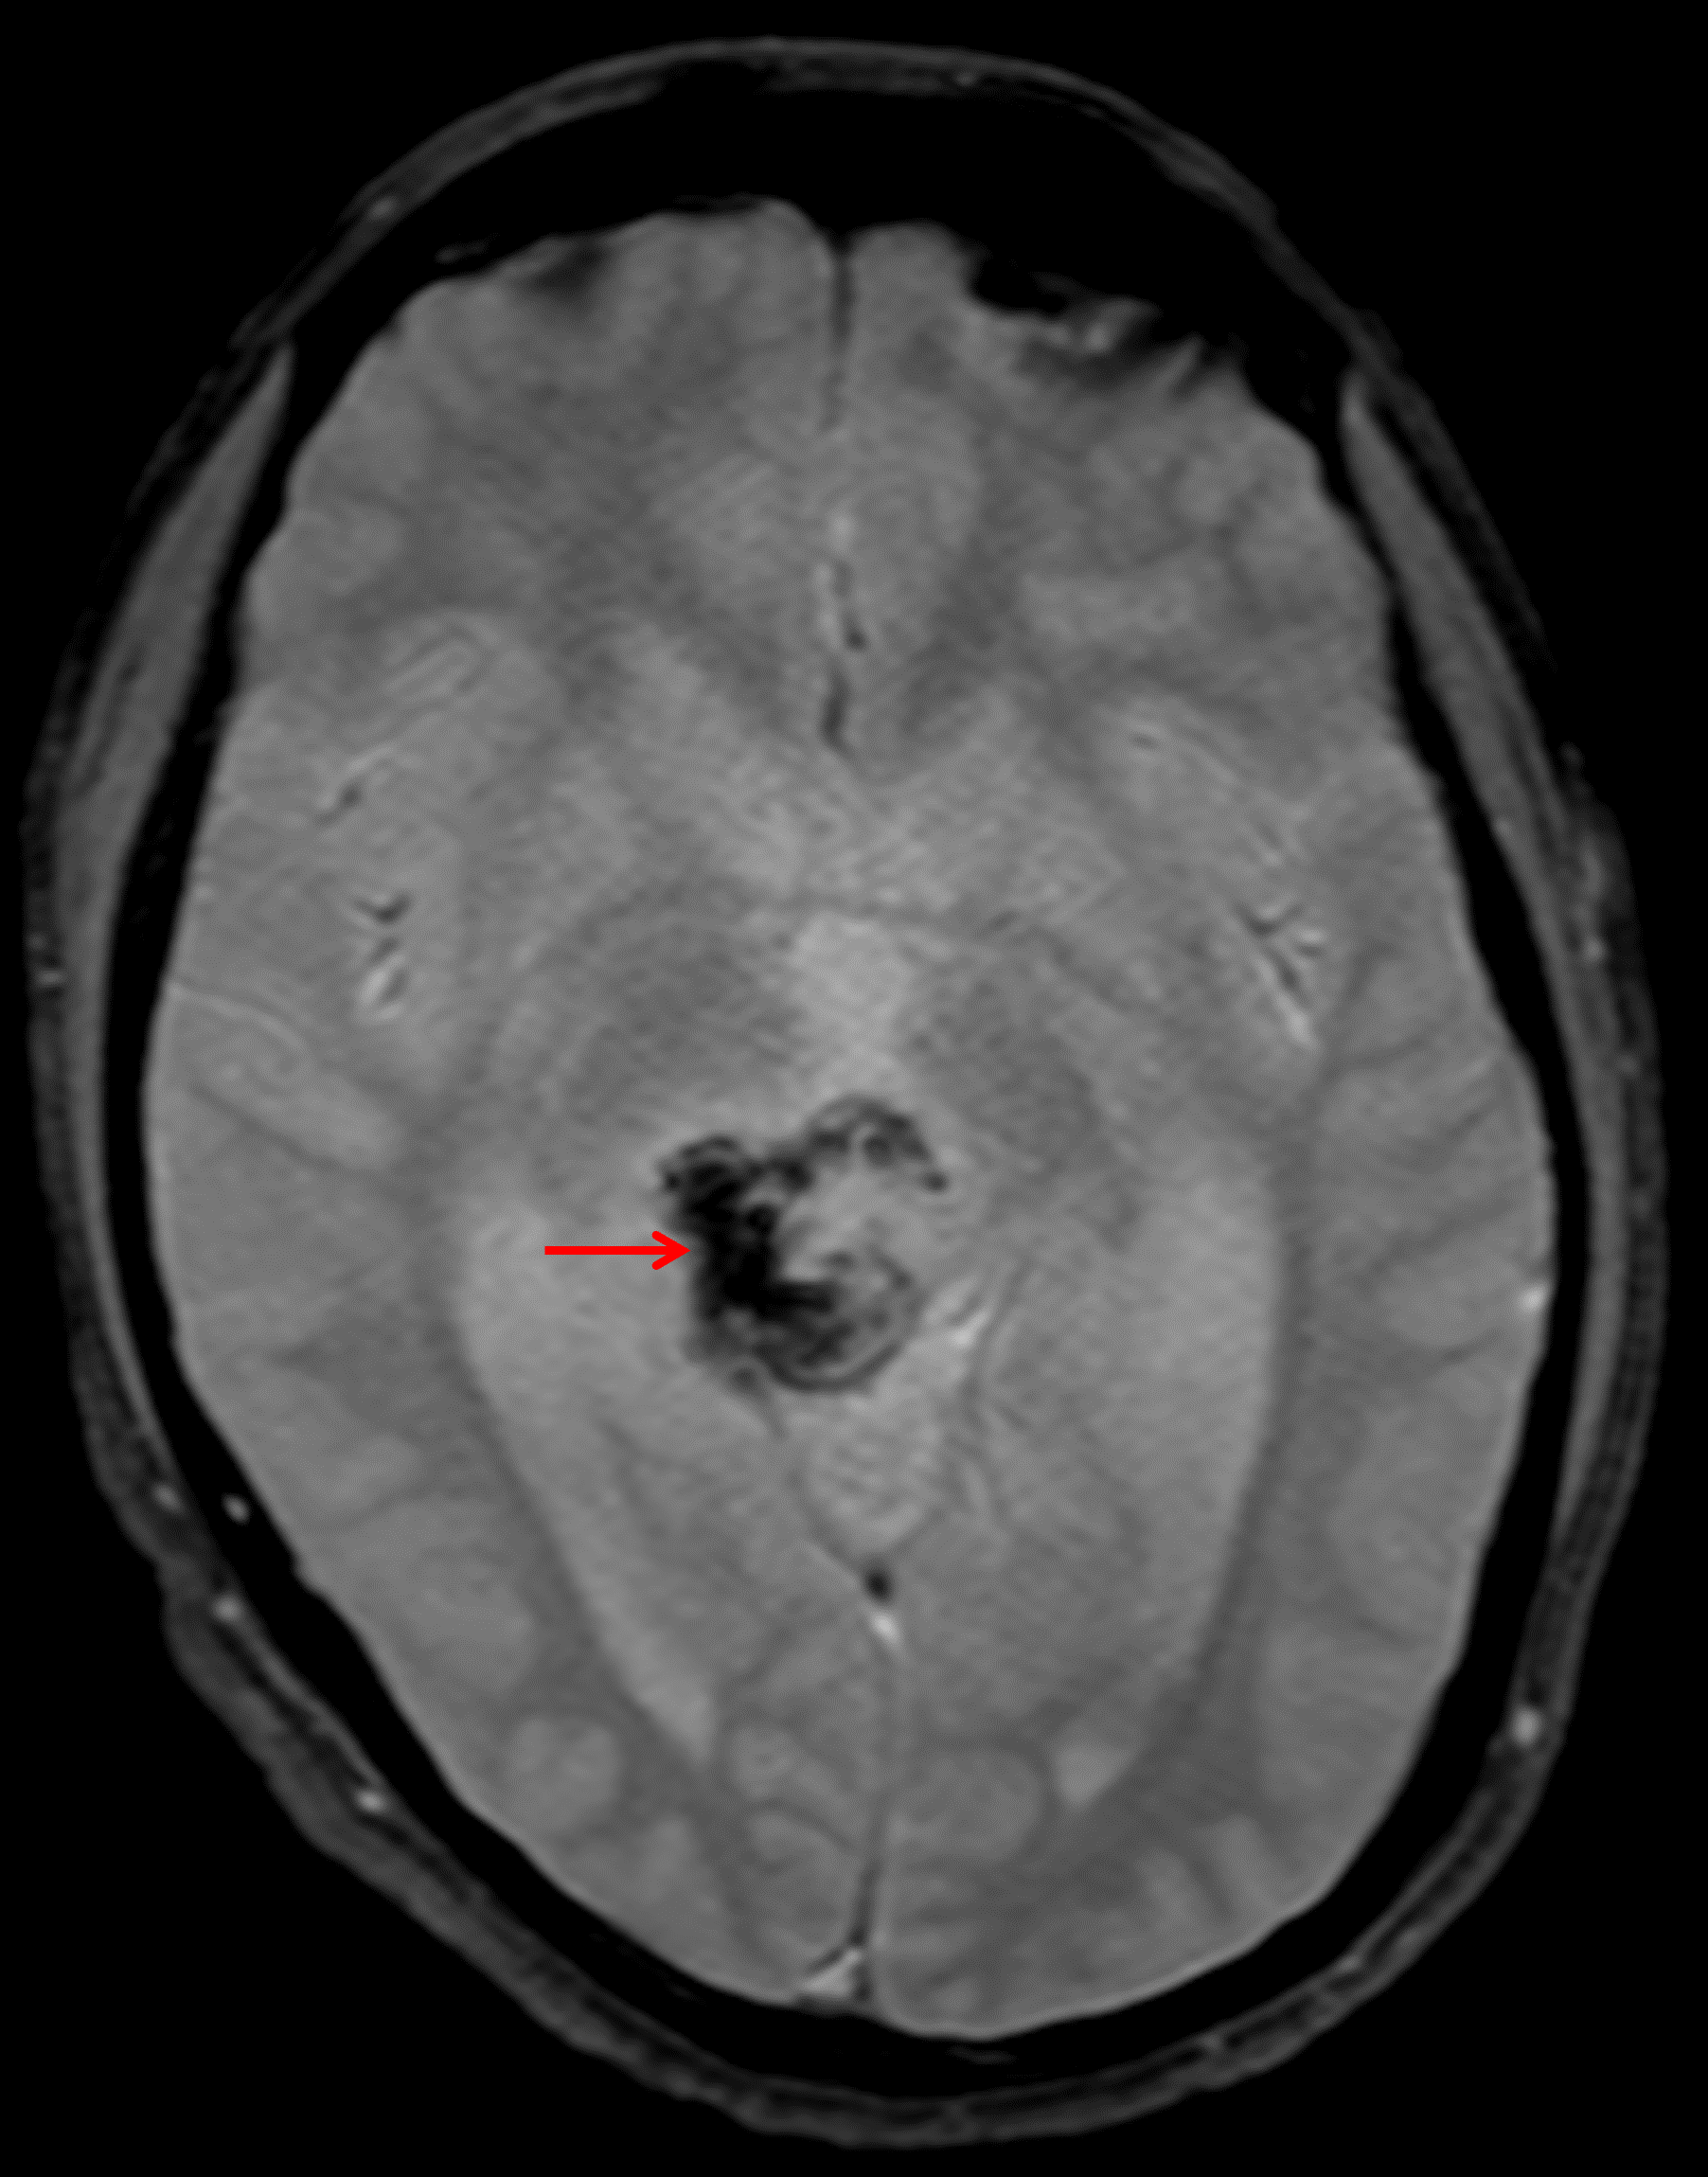

Age: 17

Sex: Male

Indication: Diplopia

Teratoma (pineal region)